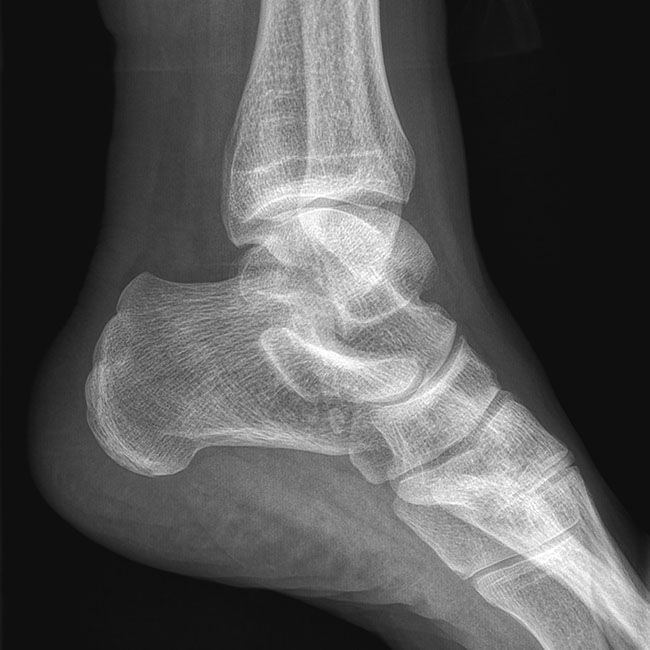

臨床樣本